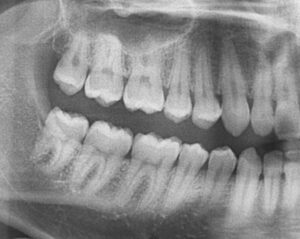

無料メール相談3(親知らずは抜歯した方が良いですか?)

今まで、多くの方々に無料でメール相談をしてきました。その中から良くある相談を紹介しています。 「歯医者で、親知らずの抜歯を勧められました。抜かないといけないですか?」とか 「親知らずを抜くとすごく腫れて痛いと聞いたのですが、本当ですか?」と […] 本文を読む